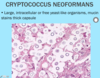

A: Describe the Histology (2)

B: Dz

Ichthyosis Vulgaris

Orthokeratosis = Thickening of Stratum Corneum = Hyperkeratosis without Parakerotosis

A: Describe Histology

B: Dz

Ichthyosis Vulgaris